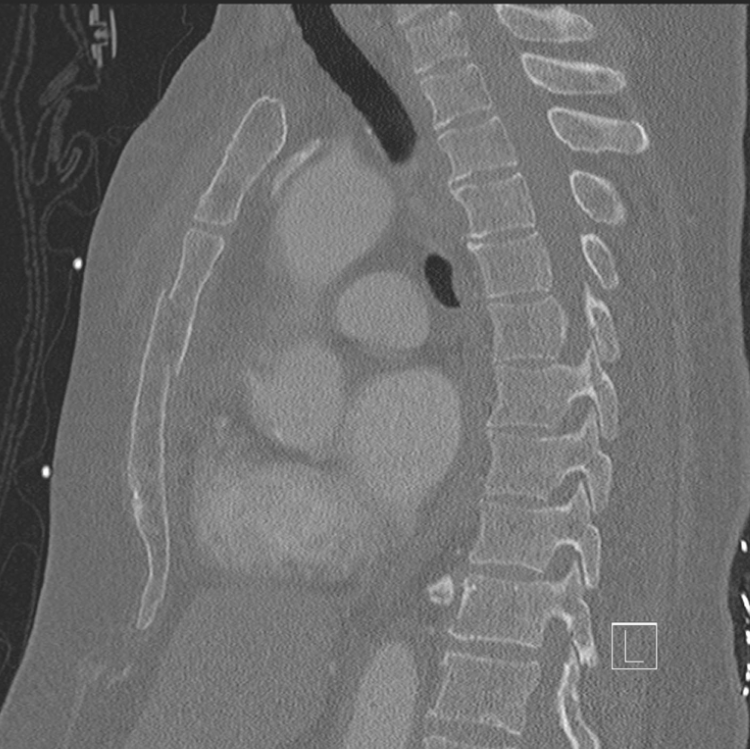

Don’t Go Breaking My Heart

A 45-year-old male presents to the emergency department with chest pain after a high-speed motor vehicle accident where his chest hit the steering wheel. He is complaining of central chest pain and there is ecchymosis noted over his sternum.